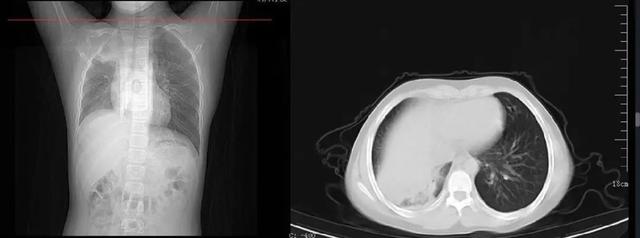

周周的影像学检查结果

接诊的儿科主任张雪荣经过一系列的查体后初步判断周周已经发展成肺炎了,“收治入院后查胸片显示,孩子右肺内见片状软组织样高密度影,右肺野内亦可见片状高密度影,考虑右肺部分不张伴胸腔积液可能。”看到胸片上患儿的一侧肺部组织大面积变白后,家长既自责又后悔。好在经中西医结合治疗后,周周目前的症状已经明显好转。